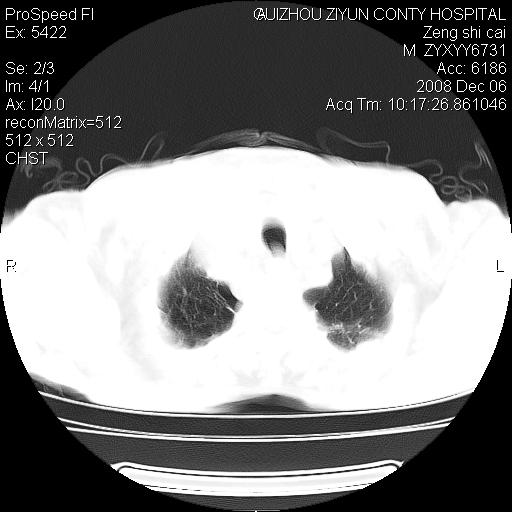

标题: CT16961:M、71岁,咳嗽半年,无血痰;胸片示右肺占位。 [打印本页]

标题: CT16961:M、71岁,咳嗽半年,无血痰;胸片示右肺占位。

右肺癌并纵隔淋巴结及胸膜转移可能性大

右肺癌并纵隔淋巴结及胸膜转移。建议气管镜

右肺纵隔型肺癌伴纵隔淋巴结及胸膜转移!

右肺纵隔型肺癌伴纵隔淋巴结转移!双侧胸水!

1)考虑右肺上叶纵隔型肺癌伴纵隔淋巴结转移。2)心包积液,双侧胸腔积液。

右肺癌并纵隔淋巴转移,腹膜后转移可能性大,两侧胸腔积液

右肺上叶纵隔型肺癌伴纵隔淋巴结转移。心包积液,双侧胸腔积液。

建议强化!主要鉴别是淋巴瘤与肺癌淋巴结转移。